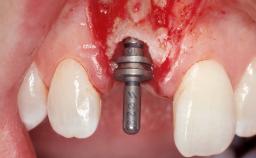

Immediate Placement of an Implant in a Maxillary Left Central Incisor Site

A 33-year-old female patient presented with an upper left central incisor that required extraction after a failed endodontic therapy. The tooth had been traumatized when the patient was a teenager and had undergone several endodontic treatments, including two apicectomy procedures. The patient was in good health and did not smoke. Clinical examination showed that the patient had a high lip line. In full smile, the gingival margins of the upper teeth were visible to the first molars. The gingival margins of central incisors 11 and 21 were only just showing. Examination of tooth 21 confirmed that the tooth was mobile and had hypererupted by 1 mm.

| Placement Protocol | Immediate implant placement |

| Tooth Site | Maxillary incisor or canine |

| Socket Morphology | Single-root socket |

| Socket Integrity | Damage to one or more bone walls |